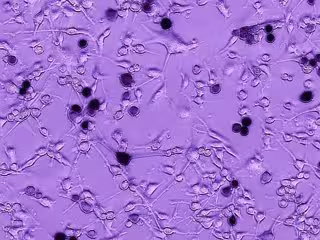

Células de glioblastoma de un cerebro humano están creciendo. La adición del virus oncolítico Ebola-VSV produce infección tumoral y muerte celular, vista aquí como células negras. Con el tiempo, la infección se propaga a otras células de glioblastoma.

Células de glioblastoma de un cerebro humano están creciendo. La adición del virus oncolítico Ebola-VSV produce infección tumoral y muerte celular, vista aquí como células negras. Con el tiempo, la infección se propaga a otras células de glioblastoma. - A VAN DEN POL